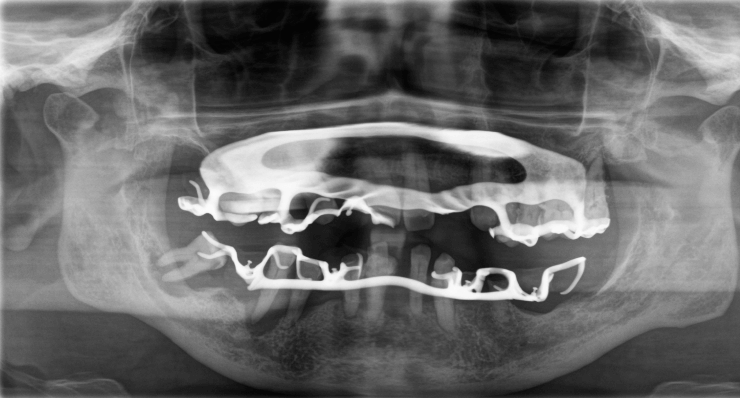

Die Prothesen waren durch Zahnsteinverblockungen und Gingivahyperplasien nicht mehr herausnehmbar.

OPG nach Entfernung von Zahnstein, Gingivahyperplasien und Prothesen (inklusive Zahn 47 ).